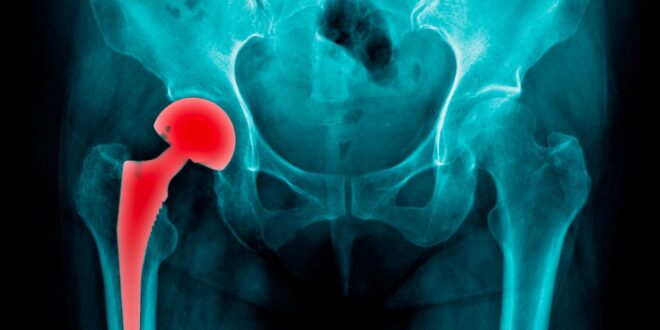

Arthrose de la hanche

Arthrose de la hanche: 80 % des patients perdent leur mobilité et 25 % limités dans les activités quotidiennes

La douleur et la raideur articulaire de l’arthrose de la hanche ont un impact direct sur la mobilité et la capacité des personnes affectées à être physiquement actives. Selon une étude 80 % des patients présentent ainsi une perte de mobilité et 25 % se retrouvent limités dans les activités quotidiennes.

L’arthrose est la maladie articulaire la plus répandue touchant environ 240 millions de personnes dans le monde. L’arthrose de la hanche se traduit le plus souvent par des douleurs musculosquelettiques sévères et une limitation des mouvements articulaires qui diminuent progressivement l’autonomie et la qualité de vie des patients concernés.

Selon une étude, la douleur et la raideur articulaire ont un impact direct sur leur mobilité et leur capacité à être physiquement actif : 80 % des patients présentent ainsi une perte de mobilité et 25 % se retrouvent limités dans les activités quotidiennes. Marcher, en particulier, devient difficile, en raison de schémas locomoteurs altérés (tels qu’une boiterie, une asymétrie de marche, etc.), associés à une vitesse de marche réduite, à une réduction de la force musculaire de la hanche et à un coût énergétique plus élevé par rapport aux personnes ne présentant pas d’arthrose. Cette situation mène les patients à devenir moins actif physiquement, ce qui a pour conséquence une importante sédentarité. Mais les effets délétères de l’arthrose de la hanche ne se limitent pas aux seuls problèmes physiques.